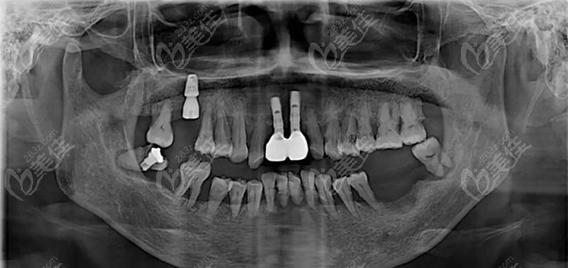

种牙前是否需要拍片,是许多准备接受种植牙手术的患者关心的问题,从临床实践来看,拍片不仅是必要的,更是保障种植牙成功和安全的关键环节,种植牙手术并非简单的“种螺丝”,而是需要通过精准的影像学检查,全面了解患者的口腔内部情况,从而制定个性化的治疗方案,避免术中损伤重要解剖结构,确保种植体能够长期稳定存在于牙槽骨中。

种植牙的核心原理是将人工种植体(相当于人工牙根)植入牙槽骨内,通过骨结合实现与骨组织的融合,再在上方安装牙冠,恢复牙齿的形态与功能,这一过程对牙槽骨的条件、周围解剖结构的要求极高,而拍片正是获取这些关键信息的“眼睛”。

评估牙槽骨的质量与数量是拍片的核心目的之一,牙槽骨的高度、宽度、密度直接影响种植体的稳定性和长期成功率,缺牙后牙槽骨会逐渐萎缩,若骨量不足,可能需要植骨或上颌窦提升等额外手术;若骨密度过低(如骨质疏松严重),种植体与骨的结合效率会降低,甚至导致失败,通过影像学检查,医生可以准确测量骨量,判断是否具备直接种植的条件,或需要何种骨增量方案。

规避神经血管损伤风险至关重要,颌骨内分布着重要的神经(如下牙槽神经)和血管(如上颌窦血管),若种植体植入位置不当,可能损伤这些结构,导致下唇麻木、出血等并发症,拍片能清晰显示这些解剖结构的位置和走向,帮助医生规划种植体的植入角度、深度,确保安全区域。

排查口腔潜在病变也是拍片的重要作用,患者可能存在牙根残留、囊肿、炎症、骨化性纤维瘤等问题,这些病变若术前未被发现,可能影响种植体愈合,甚至导致手术失败,拍片能帮助医生全面评估口腔健康状况,必要时先进行治疗再进行种植。

CBCT因三维成像的优势,已成为现代种植牙术前检查的重要手段,对于上颌后牙区种植,CBCT能清晰显示上颌窦底的位置和骨壁厚度,判断是否需要上颌窦内提升或外提升;对于下颌后牙区,可精准标记下牙槽神经管的位置,避免种植体进入神经管。